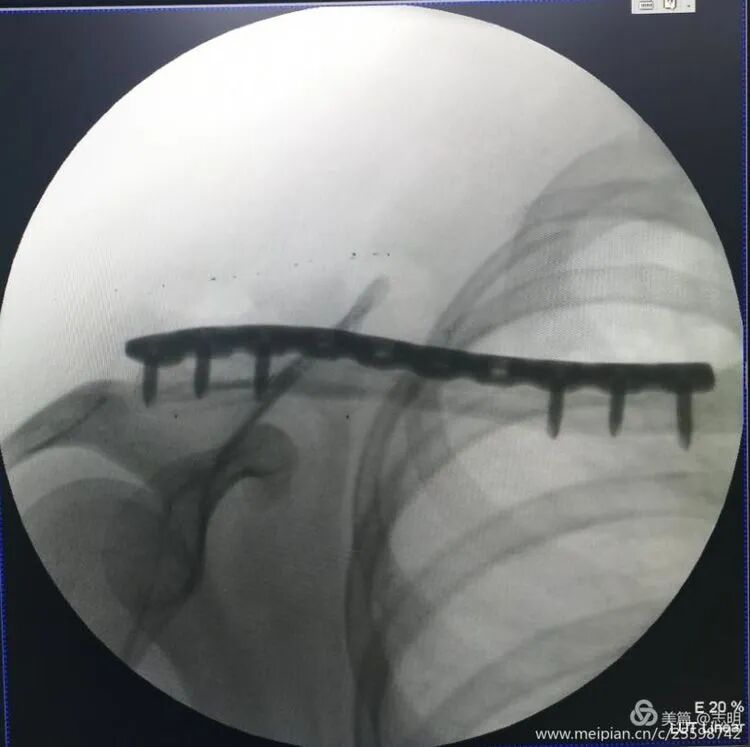

Plate Insertion and Screw Fixation

- Plate Passage: Once the fracture reduction is deemed satisfactory and secured with temporary fixation, the pre-contoured locking plate is carefully passed through the previously created subcutaneous tunnel. Specialized plate manipulators and guides are used to ensure the plate lies snugly and flush against the superior or anterosuperior cortical surface of the clavicle.

(Image depicting the insertion of a plate through a small incision).(Fluoroscopic image confirming proper plate positioning).(Another fluoroscopic view illustrating the plate's final position).

- Screw Insertion:

- Begin by drilling and inserting screws in both the proximal and distal main fracture fragments through the small skin incisions. Utilize percutaneous drill guides and specialized screw drivers designed for MIPO techniques.

- Screw Length and Trajectory: Exercise extreme caution when selecting screw length to ensure adequate bicortical purchase without over-penetration, which carries a significant risk of damaging underlying neurovascular structures. Fluoroscopy, again in both AP and lateral/cephalic tilt views, is paramount for real-time assessment of screw trajectory and length.

- Screw Type and Sequence: For comminuted fractures, locking screws are generally preferred to provide angular stability and maintain reduction indirectly. In simpler fracture patterns, an initial lag screw or a compression screw (if the plate design permits dynamic compression) can be employed to achieve optimal interfragmentary compression, followed by the insertion of locking screws to complete the construct.

- Final Intraoperative Assessment: Once all screws are securely inserted, perform a comprehensive final fluoroscopic assessment. Verify satisfactory fracture reduction, confirm stable and flush plate position, and ensure appropriate screw lengths and trajectories. Any temporary K-wires are then removed.